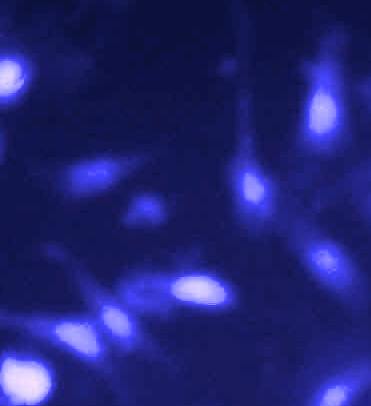

Hoescht staining

The U-87 MG Cells were treated by GCB loaded with MPEG-PCL nanoformulation (GCBNP 3) which shows maximum intracellular accumulation. The cellular uptake of GCB loaded MPEG-PCL nanoparticles in U-87 MG cells were examined under fluorescence microscopy and the images are shown in fig.11.

The results showed significant apoptotic cell death in GCB loaded MPPEGPCL nanoformulation compared with the pure drug. This indicates that the nanoformulation penetrates the cell membrane of glial cells.

Fig. 11: Comparison of penetration of control, pure drug, PNP and GCBNP 3 in U-87 MG cell lines using Hoechst 33342 DNA staining technique